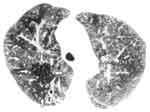

Определенное диагностическое значение имеет симптом утолщения стенок бронхов. Он легче обнаруживается при поражении субсегментарных бронхов в форме почти параллельно расположенных теневых полосок (симптом "трамвайных рельсов", "тубулярных теней"), между которыми вырисовывается просвет бронха (Рис. 2). Каждая полоска представляет собой суммарную тень стенки бронха и перибронхиального склероза. Стенки более мелких бронхов часто плохо улавливаются на рентгенограммах, но можно заметить узкие, разделяющиеся в дистальном направлении просветы бронхов. Конечно, состояние стенок и просветов бронхов, бронхиальные расширения и бронхоэктазы несравненно лучше выявляются при КТ.

Рис. 2. Симптом "трамвайных рельсов" (указан стрелками). (Слева) Фрагмент рентгенограммы.

(Справа) Компьютерная томограмма.